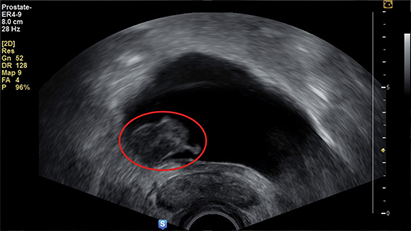

02초음파 검사는 초음파 검사기를 통해 혈뇨를 검사합니다.

초음파 검사기를 통해 혈뇨를 검사합니다.

신장결핵, 방광염, 전립선 질환 등